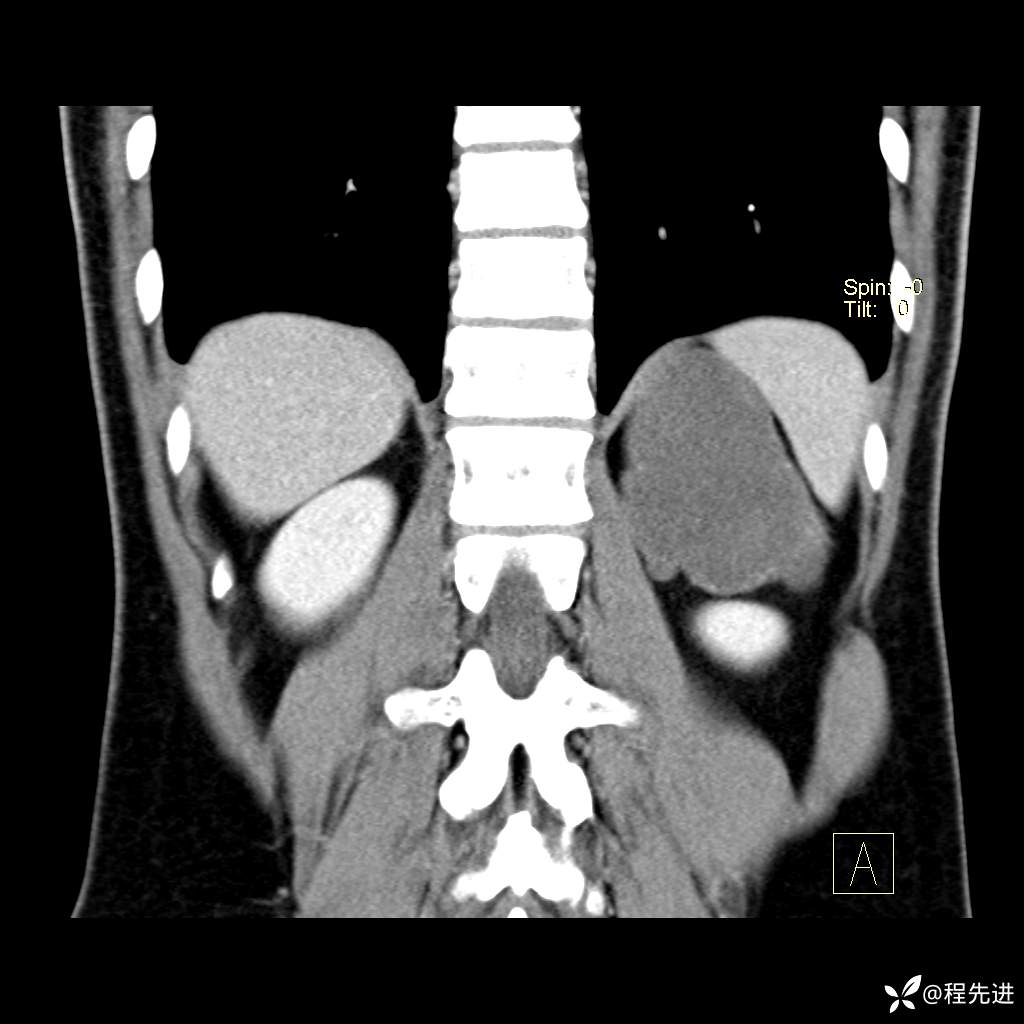

CT平扫:(CT值:平扫,27HU,动脉期,27HU,门静脉期,31HU,平衡期,32HU)

冠状位重建: